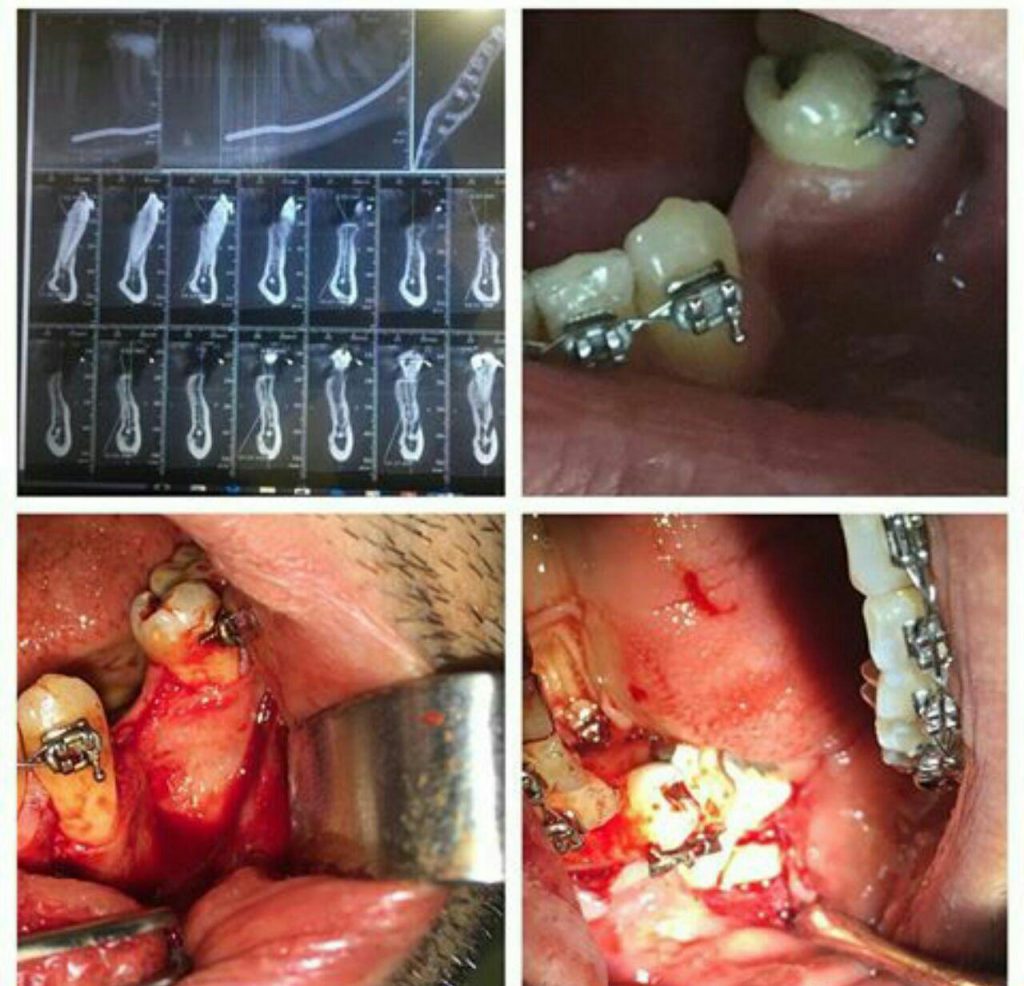

جراح دندانپزشك

متخصص بيماريهاي دهان، فك و صورت

فلوشيپ ايمپلنت از ICOI آمريكا

گواهينامه ايمپلنت و زيبايي از دانشگاه UCLA آمريكا